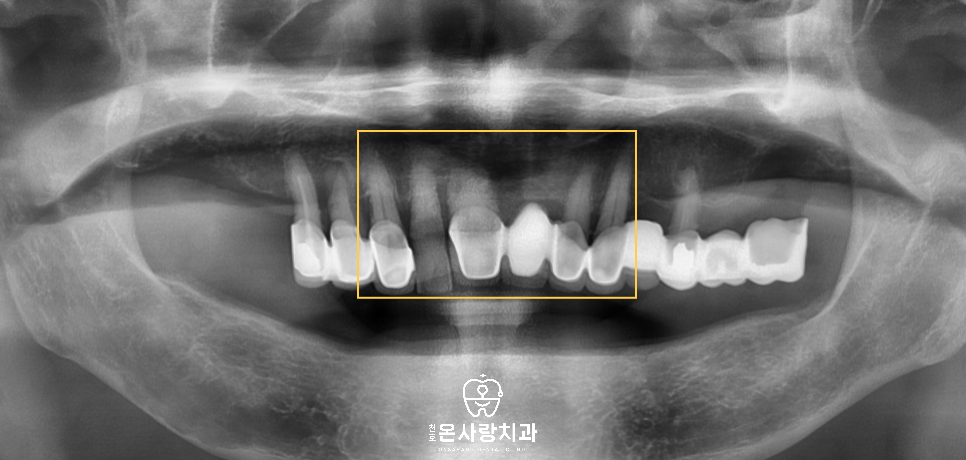

이렇게 가능한 한 자연치를

보존하는 이유는 남아 있는

치아가 보철물의 지지 역할을

해줄 뿐만 아니라 감각적 균형감을

유지하는 데에도 중요하기 때문입니다.

자연치가 완전히 없는 경우보다

잔존 치아가 일부라도 존재하면,

전체적인 안모에 맞는 교합의

높이와 저작 패턴을 보다

자연스럽게 재현할 수 있습니다.